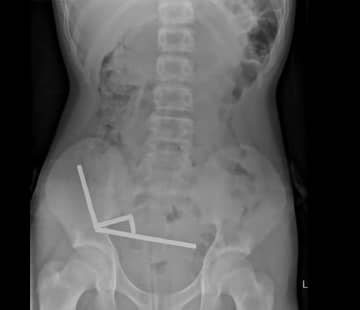

超強力磁石を大量にのみ込んだ13歳少年、腸の壊死で一部を摘出 NZ (CNN) ニュージーランドで13歳の少年が超強力磁石80個あまりをのみ込み、病院で腸の一部を摘出す... CNN.co.jp | Tue, 28 Oct 2025 10:49:20 +0900 もっとよむ Pick Up 2025年10月09日 「ちみたん× 選べるニュース」のLINEスタンプを無料でGET! チバテレ+プラス ライフ 2024年03月07日 【新商品!】チュバチュバワンダーランドに新たなグッズが登場★ チバテレ+プラス ライフ